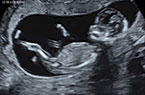

Grossesse de 12 SA - foetus et annexes foetales - images cliniques Grossesse de 12 SA - foetus et annexes foetales - images cliniques Grossesse de 12 SA - foetus et annexes foetales - images cliniques